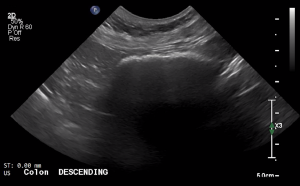

SIMON Ultrasound Database

This ultrasound database is a free resource for students and doctors!

Our collection includes videos of dogs, cats, horses, cows, humans, and many other species!